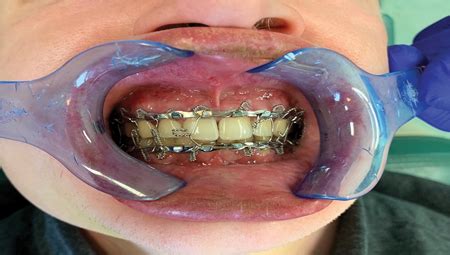

16+ Wiring Jaw Shut Surgery - MarcelWillum